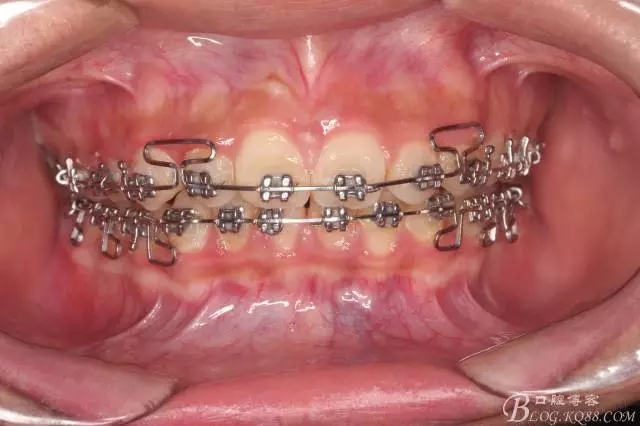

看看口內(nèi)照吧!真象“大暴牙”v假象“大暴牙”

三度深覆合,三度深覆蓋,尖牙,磨牙均二類關系!